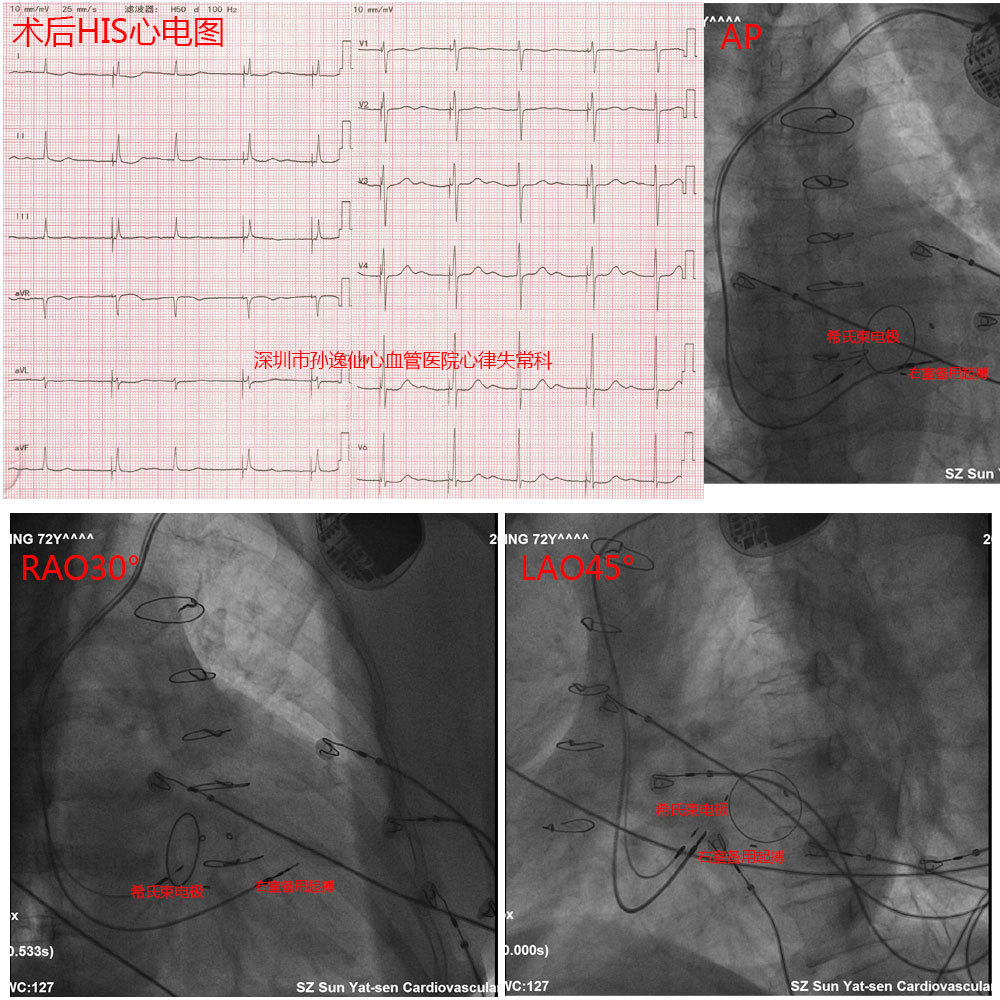

希氏束起搏心电图解读一例

我院成功施行市内首例希氏束起搏治疗房室传导阻滞患者

山西省人民医院心内二科电生理团队独立完成两例希氏束起搏

最生理的起搏——希氏束起搏

希氏束起源室性心律失常心电图特点

缓慢性心律失常患者的福音——永久性希氏束起搏

心血管内科二病区成功实施医院首例希氏束起搏术